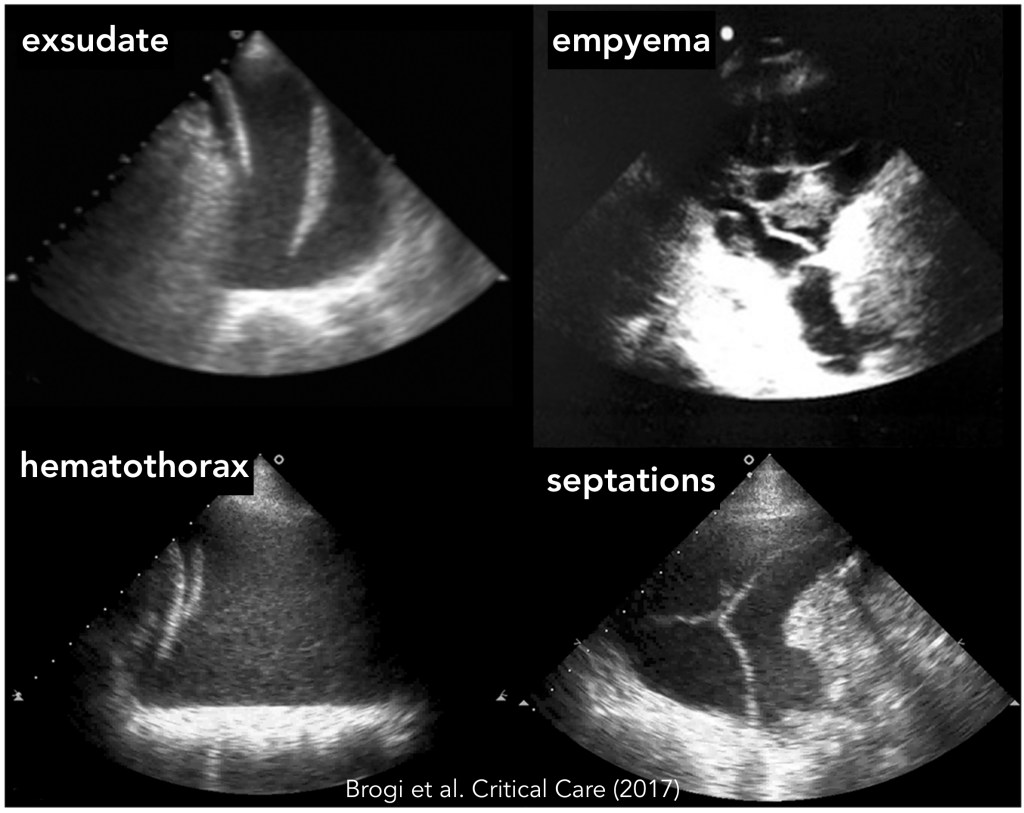

Pleural effusion